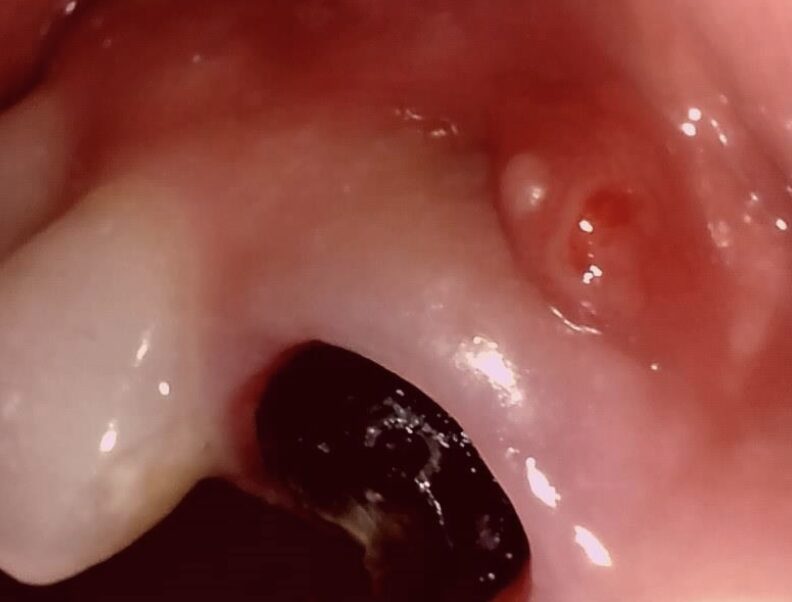

初診時の状態|前歯の歯ぐきに腫れとできものが見られました

初診時、右上の前歯周囲には炎症による腫れが見られました。

歯の根の中で破折が起こり、そこから細菌が侵入したことで、根の先に膿がたまっている状態でした。

初診時の口腔内写真②